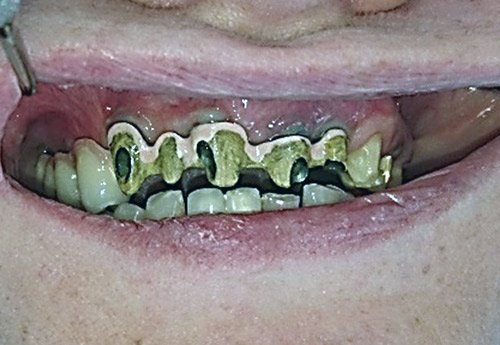

Prosthetic solutions of complicated bite conditions